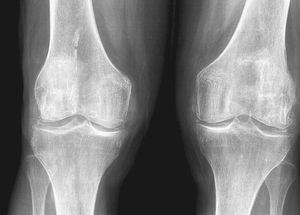

Las exploraciones complementarias mostraron un hemograma y bioquímica normales con calcio, fósforo y uricemia dentro de los límites de la normalidad. La velocidad de sedimentación globular y la proteína C reactiva fueron normales y el factor reumatoide negativo. La radiología (Rx) objetivó signos degenerativos en las articulaciones fémoro-tibiales con la presencia de calcificaciones meniscales (fig. 1); la Rx de manos mostró calcificación de ligamento triangular del carpo y signos degenerativos de interfalángicas proximales y distales. La Rx del hombro (fig. 2) izquierdo mostró fragmentos osteocondrales, excrecencias óseas en articulación escápulo-humeral con signos degenerativos y calcificaciones. El líquido articular de la rodilla izquierda fue de características mecánicas, con presencia de cristales de pirofosfato cálcico dihidratado al visualizarlo por microscopio de luz polarizada; los cultivos fueron negativos.

Figura 1. Radiografía de ambas rodillas. Disminución espacio fémoro-tibial bilateral, osteofitos marginales, esclerosis subcondral, calcificación meniscos.